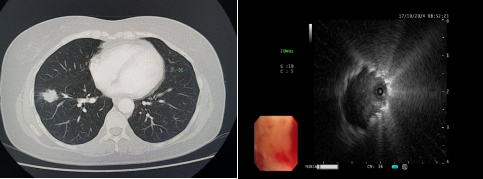

患者,女性,于10天前无明显诱因出现咳嗽,干咳为主,未予以重视,之后仍咳嗽、咳痰,就诊于外院,胸部CT提示双肺纹理增粗、右肺门团块影、右肺下叶前基底段实性结节团。为求进一步诊治转入我院呼吸与危重症医学科。入院后完善相关检查,于10月17日9时安排气管镜检查,副主任医师韩蓓与主管护师薛冬冬为患者行气管镜检查,镜下示:双肺支气管均未见明显异常,结合CT给予超声探查,于右肺下叶前基底段亚支探及偏心异常回声区,由于亚支位置较远且管腔较窄,活检钳无法到达,给予冷冻肺活检,成功获取3块活检标本,活检病理结果提示为恶性肿瘤。